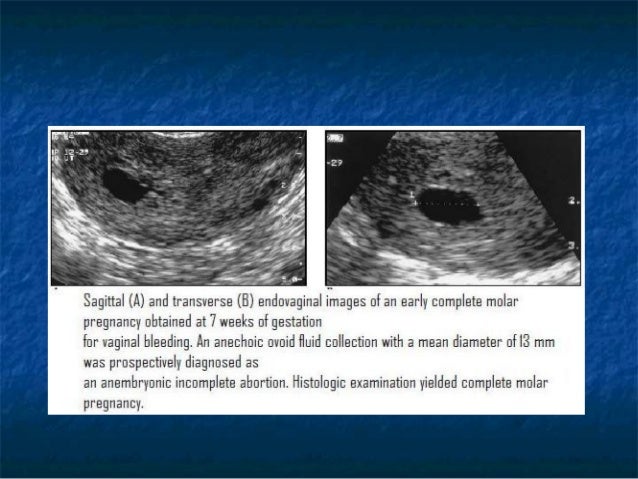

Molar Pregnancy – POCUS Journal

molar pregnancy – POCUS Journal pocusjournal.com